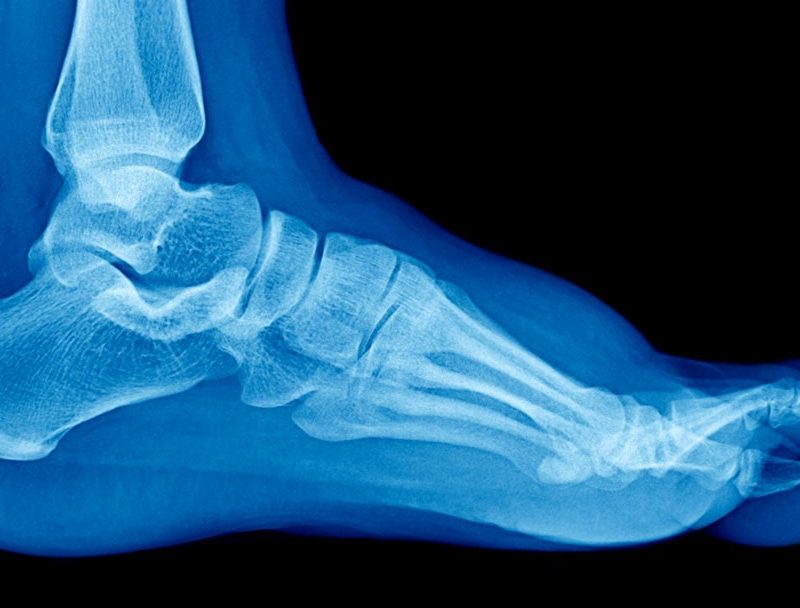

Understanding Flatfoot in Children Childhood PathologiesPathologies Understanding Flatfoot in Children